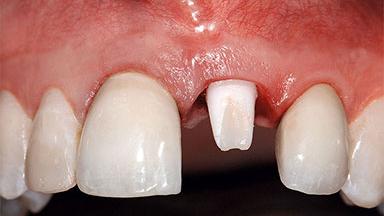

A healthy 37-year-old female patient was referred for a consultation on the replacement of missing tooth 21 with an implant-supported restoration. She stated that several years previously the tooth had been traumatically avulsed following a motor vehicle accident. The tooth was replaced with a three-unit fixed partial denture (FPD) immediately afterwards. Over time, she became disillusioned with the FPD and looked for a different option, including orthodontic therapy. She presented still in her orthodontic appliances, with the pontic sectioned free from the FPD but attached to the archwire. Her orthodontist felt that orthodontic treatment had been successfully completed, but nevertheless referred her before removing the appliances in case adjustments were necessary.

Soft Tissue Contour and Volume Slightly compromised